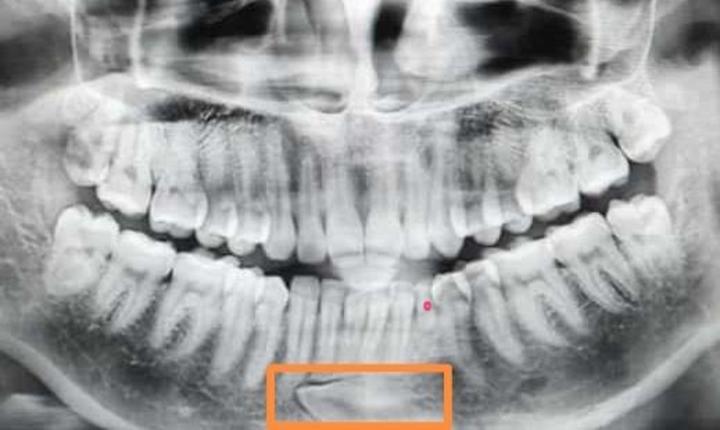

下面三个病例都是因为乳牙龋齿,乳牙滞留,导致对应恒牙阻生。特别提醒:1.重视乳牙龋齿的防治。2.换牙期间6——12岁至少每半年口腔检查一次,及时发现换牙异常,及时干预。

红点处是龋齿滞留的乳牙,方框里是埋伏阻生的恒牙。